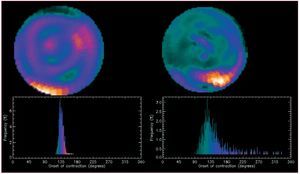

Uno de los avances metodológicos más interesantes en la SPECT de perfusión miocárdica es la introducción del análisis de Fourier para la valoración de la sincronía del ventrículo izquierdo115,116. Esta metodología ya se viene aplicando a la ventriculografía isotópica de equilibrio, en la que, además de la sincronía intraventricular, también es posible valorar la sincronía interventricular117,118. El análisis de mapas polares y, sobre todo, el histograma de fase de la SPECT de perfusión miocárdica (fig. 5) permite cuantificar con excelente reproducibilidad119 la disincronía del ventrículo izquierdo, lo que abre la posibilidad de añadir información pronóstica sobre pacientes con desfibrilador120 y en la detección de enfermos no respondedores a la terapia de resincronización121,122.

Figura 5. Mapas polares e histograma de fase del ventrículo izquierdo (análisis de Fourier) obtenidos a partir de una tomografía por emisión monofotónica de perfusión miocárdica. A la izquierda, un ejemplo de normalidad en la sincronía de contracción ventricular y, a la derecha, un ejemplo de marcada disincronía claramente objetivable en la anormal amplitud del histograma de fase.